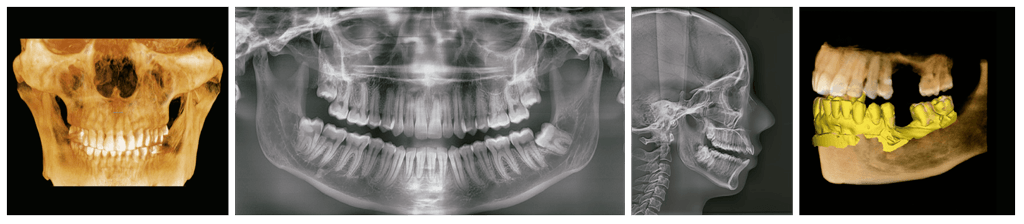

EL SISTEMA MÁS AVANZADO DE RAYOS X DIGITAL 4 EN 1

Green X incorpora pano, ceph (opcional), CBCT y escaneo de modelos.

Proporciona imágenes de alta calidad con menor radiación al combinar el procesamiento de imágenes con la amplia experiencia de Vatech en el campo de las imágenes dentales, mejorando la precisión de tu diagnóstico y una mejor planificación del tratamiento.